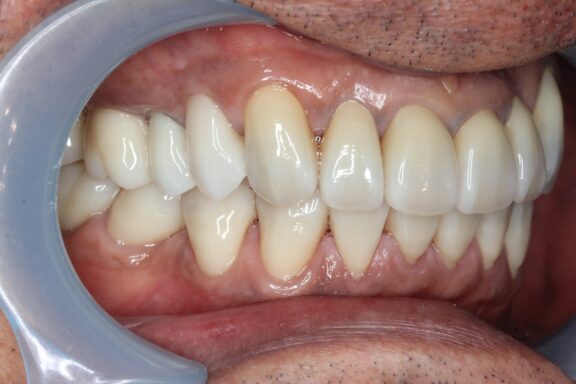

完成がこちらになります。

術前、術後で比較すると、とても口腔内が明るくなり、正面から見てもとても若々しく感じます